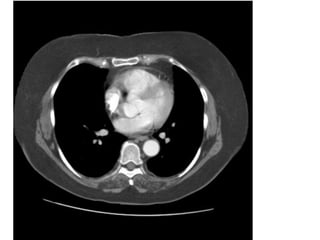

Figure 25b. PE cấp ở bn nam 59 tuổi.

(b) CT scan (window width = 552 HU, window level = 276 HU) cho thấy PE cấp

ở nhánh trong của đm thùy giữa (P). (mũi tên) dấu hiệu này không thấy trên

hình 25a.

3

2